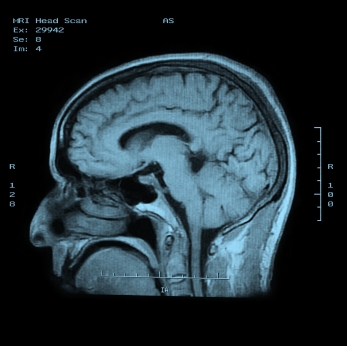

ДИАГНОСТИКА

Диагноз не вызывает серьезных затруднений. Для уточнения точных причин гидроцефалии проводятся: КТ, МРТ, рентгенография черепа, пневмоэнцефалография, вентрикулография, ангиография, УЗИ черепа (особенно у детей раннего возраста), люмбальная пункция с измерением давления спинномозговой жидкости.

Медицинские процедуры, проводимые при заболевании гидроцефалия: Спиральная компьютерная томография, Магнитно-резонансная томография, Рентгенография черепа, Пневмоэнцефалография, Вентрикулография, Ангиография, УЗИ, Измерение давления спинномозговой жидкости